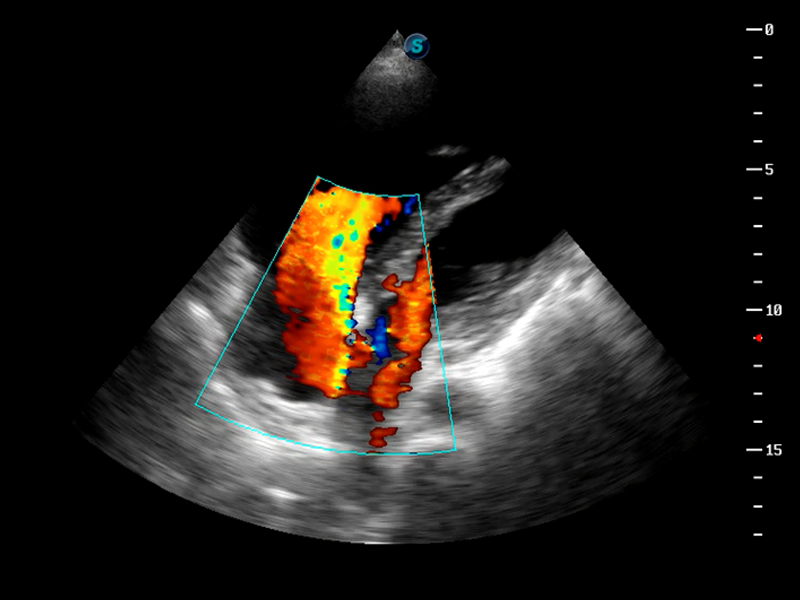

S9便携式彩色多普勒超声诊断仪是新葡的京集团8814检测站研发的高端便携彩超设备,外观设计新颖、产品性能卓越。S9在便携超声领域采用了突破传统的触摸屏交互设计,并以先进的软件硬件技术和设计理念,为您带来清晰的图像质量、稳定的工作性能和便捷的操作体验。

AutoC智能血流追踪